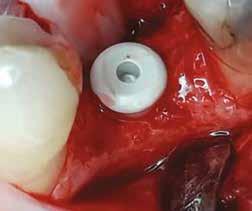

Mind a hat implantátum esetén kétlépcsős műtétet végeztünk. Minden sebészeti eljárást bódítás, illetve preoperatív szisztémás antibiotikus terápia nélkül végeztünk. A négy eset közül kettőnél leukocitában és vérlemezkében gazdag fibrint (L-PRF) alkalmaztunk a beavatkozás során (IntraSpin, BioHorizons; 2. táblázat). Minden esetben a pontos CERALOG menetvágási (maximum 15 ford./perc) és fúrási (maximális fúrási fordulatszám: 550–800 ford./perc) protokollt követtük. Az összes implantátumot manuálisan helyeztük be 35 Ncm maximális nyomatékkal. Az implantátumokba PEEK zárócsavar került (2. ábra). A lágyszövetet atraumatikus, felszívódó varrattal, szorosan zártuk/összevarrtuk. A műtétek után szövődmények nem jelentkeztek. A pácienseket arra kértük, hogy a műtét utáni héten naponta kétszer öblögessenek klórhexidinnel (PERIO-AID, 0,05%, DENTAID). Az alsó állcsontnál három hónapos, a felső állcsontnál öt hónapos gyógyulási időt vettünk figyelembe. Három hónap (1. eset) és öt hónap (2., 3. és 4. eset) elteltével a műtétek második stádiumát helyi érzéstelenítés mellett végeztük. A gyógyu-

lási csavarokat (PEEK titáncsavarral) maximum 15 Ncm-rel húztuk meg (3–6. ábra). Az összes implantátum kiváló stabilitást mutatott (a mérésekhez Periotestet használtunk, a Medizintechnik Gulden jóvoltából), és teljesen osszeointegrálódott. Ezt a radiológiai vizsgálatok is megerősítették.

2. a–d ábra: PEEK zárócsavarok az implantátumokba helyezve, 1. eset (a). 2. eset (b). 3. eset (c), 4. eset (d). 3. a–b ábra: Röntgenfelvételek három hónap után (a) és a gyógyulási csavarok behelyezve (b, 1. eset). 4. a–b ábra: Röntgenfelvételek öt hónappal később (a) és a gyógyulási csavarok behelyezve (b, 2. eset). 2. táblázat: Az implantátum tulajdonságai.

Röntgenfelvételek öt hónappal később (a) és a gyógyulási csavarok behelyezve (b és c, 3. eset).

6. a–b ábra: Röntgenfelvételek öt hónappal később (a) és a gyógyulási csavarok behelyezve (b, 4. eset).